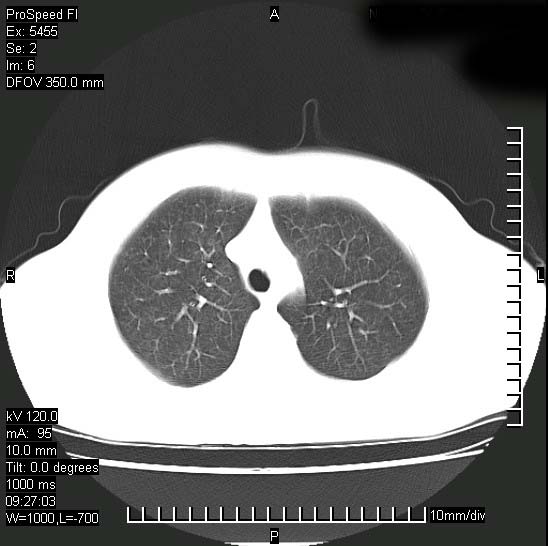

以下是引用zjzjr在2008-12-3 20:50:00的发言:[br]考虑泛细支气管肺炎,建议进一步检查除外肺出血性疾病如含铁血黄素沉着症、肺肾综合征等。

以下是引用zjzjr在2008-12-3 20:50:00的发言:[br]考虑泛细支气管肺炎,建议进一步检查除外肺出血性疾病如含铁血黄素沉着症、肺肾综合征等。

以下是引用光线在2008-12-3 20:19:00的发言:[br]双肺间质性改变。